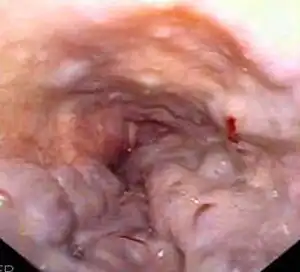

Hepatorenal syndrome usually affects individuals with cirrhosis and elevated pressures in the portal vein system (termed portal hypertension). While HRS may develop in any type of cirrhosis, it is most common in individuals with alcoholic cirrhosis, particularly if there is concomitant alcoholic hepatitis identifiable on liver biopsies.[9] HRS can also occur in individuals without cirrhosis, but with acute onset of liver failure, termed fulminant liver failure.[3][9]

Certain precipitants of HRS have been identified in vulnerable individuals with cirrhosis or fulminant liver failure. These include bacterial infection, acute alcoholic hepatitis, or bleeding in the upper gastrointestinal tract. Spontaneous bacterial peritonitis, which is the infection of ascites fluid, is the most common precipitant of HRS in cirrhotic individuals. HRS can sometimes be triggered by treatments for complications of liver disease: iatrogenic precipitants of HRS include the aggressive use of diuretic medications or the removal of large volumes of ascitic fluid by paracentesis from the abdominal cavity without compensating for fluid losses by intravenous replacement.[9]

A transjugular intrahepatic portosystemic shunt (TIPS) involves the decompression of the high pressures in the portal circulation by placing a small stent between a portal and hepatic vein. This is done through radiologically guided catheters which are passed into the hepatic vein either through the internal jugular vein or the femoral vein. Theoretically, a decrease in portal pressures is thought to reverse the hemodynamic phenomena that ultimately lead to the development of hepatorenal syndrome. TIPS has been shown to improve kidney function in patients with hepatorenal syndrome.[8][38][39] Complications of TIPS for treatment of HRS include the worsening of hepatic encephalopathy (as the procedure involves the forced creation of a porto-systemic shunt, effectively bypassing the ability of the liver to clear toxins), inability to achieve adequate reduction in portal pressure, and bleeding.[8][38]